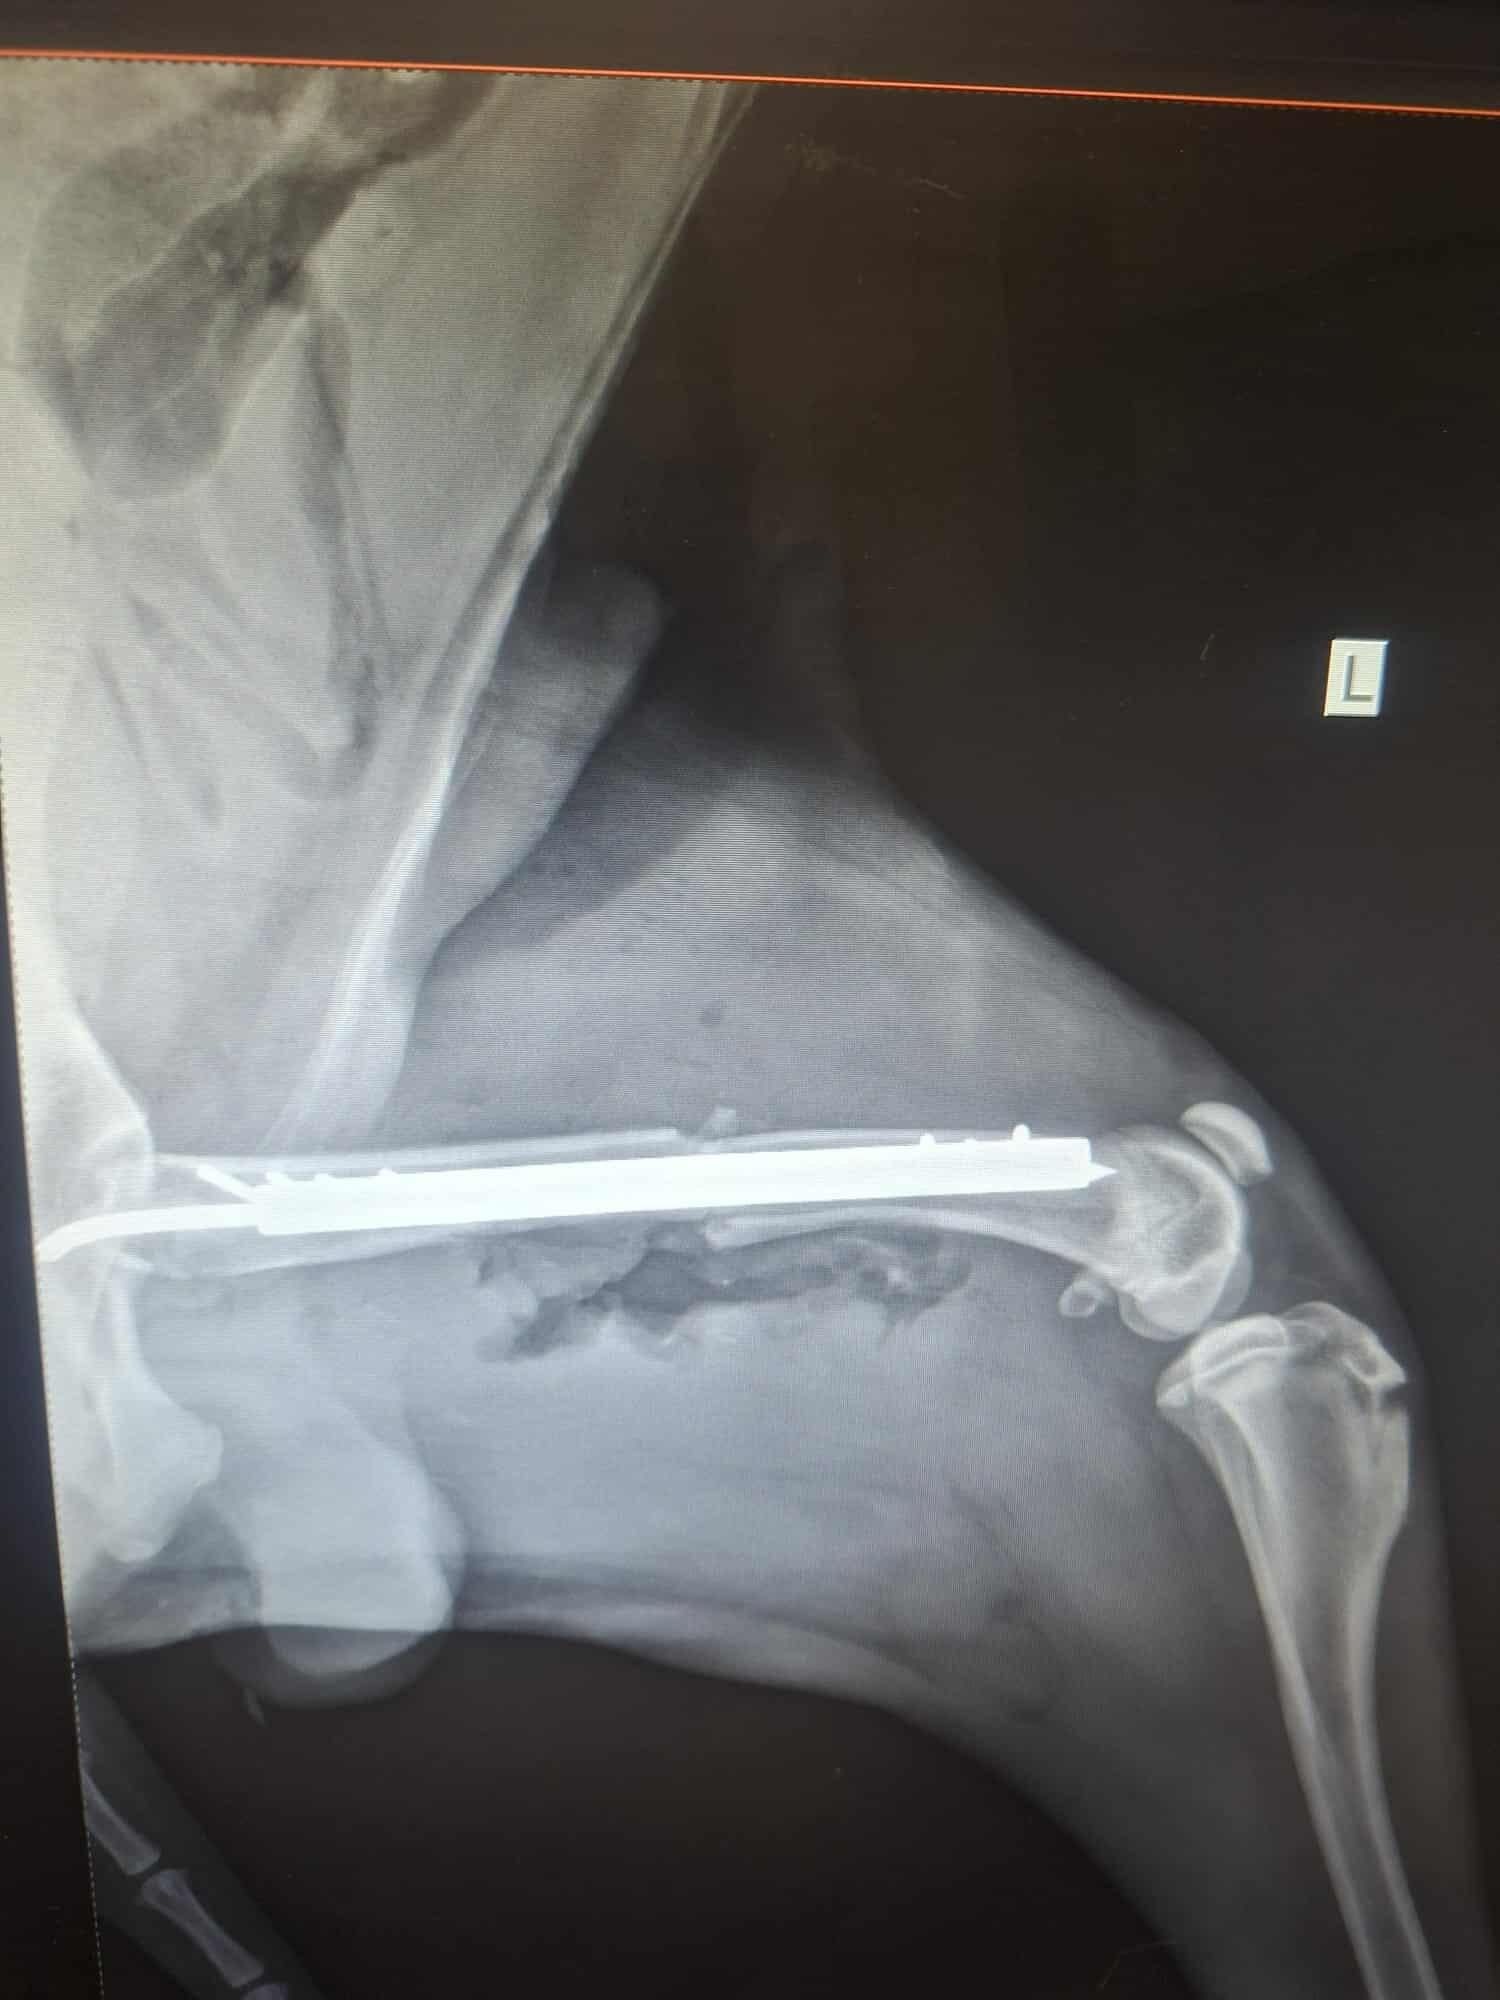

Conduit d’urgence chez le vétérinaire, le diagnostic est tombé : Lupi souffre d’une fracture du fémur et d’une fracture de la tête qui nécessite une prise en charge immédiate.